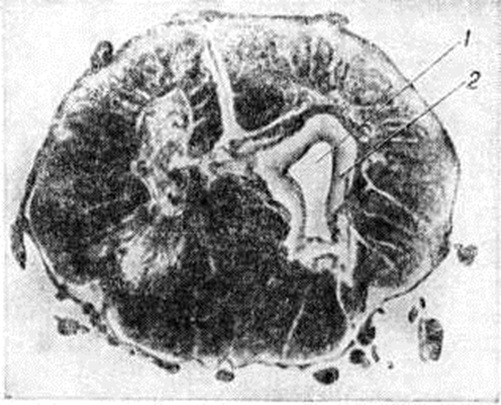

Патологическая анатомия. При макроскопическом исследовании спинного мозга обнаруживаются утолщение твёрдой и паутинной оболочек, сращения их на отдельных участках между собой и с мягкой оболочкой, уплощение, утолщение или истончение отдельных или всех его сегментов. В некоторых расширенных сегментах спинного мозга определяются также уплотнения и флюктуация. Характерные для Сирингомиелия единичные или множественные патологический полости (рисунок 1) локализуются преимущественно в центральных отделах сегментов спинного мозга, иногда и в мозговом стволе; белая спайка при этом, как правило, сохранена. Полости в большинстве случаев не связаны с центральным каналом, распространяются на задние столбы и центральные отделы задних канатиков; встречаются они и в переднем канатике. Конфигурация их разнообразна: круглая, овальная, щелевидная, в форме песочных часов, с одним или несколькими дивертикулами. Размеры полостей также различны: от узких, обнаруживаемых только при надавливании на боковые, переднюю или заднюю поверхности спинного мозга, до крупных, занимающих почти весь поперечник сегмента. Патологический полости могут быть настолько велики, что спинной мозг приобретает форму тонкостенной трубки и легко рвётся при неосторожном выделении его из твёрдой оболочки. Чаще всего полости распространяются на 1—2, реже — на большее число сегментов. Описано наблюдение, в котором полости простирались от сегмента СIII до LII. В единичных случаях полости достигают продолговатого мозга и варолиева моста (моста головного мозга. Варолиев мост, как правило, является границей распространения их в оральном направлении, однако известно наблюдение, когда щелевидная полость простиралась от крестцовых сегментов через все отделы спинного мозга, продолговатый мозг, правую половину варолиева моста, правую ножку мозга, внутреннюю капсулу, хвостатое ядро и заканчивалось у переднего рога бокового желудочка мозга.

Рис. 1. | ||

При Сирингомиелия нередко наблюдается сочетание описанных изменений с атрезией или сужением срединной и латеральных апертур четвёртого желудочка мозга, расширением желудочков головного мозга и центрального канала спинного мозга, а также с пороками развития, характерными для дизрафического статуса, с нейроэктодермальными опухолями (чаще всего со спонгиобластомами и эпендимомами) и ангиомами.